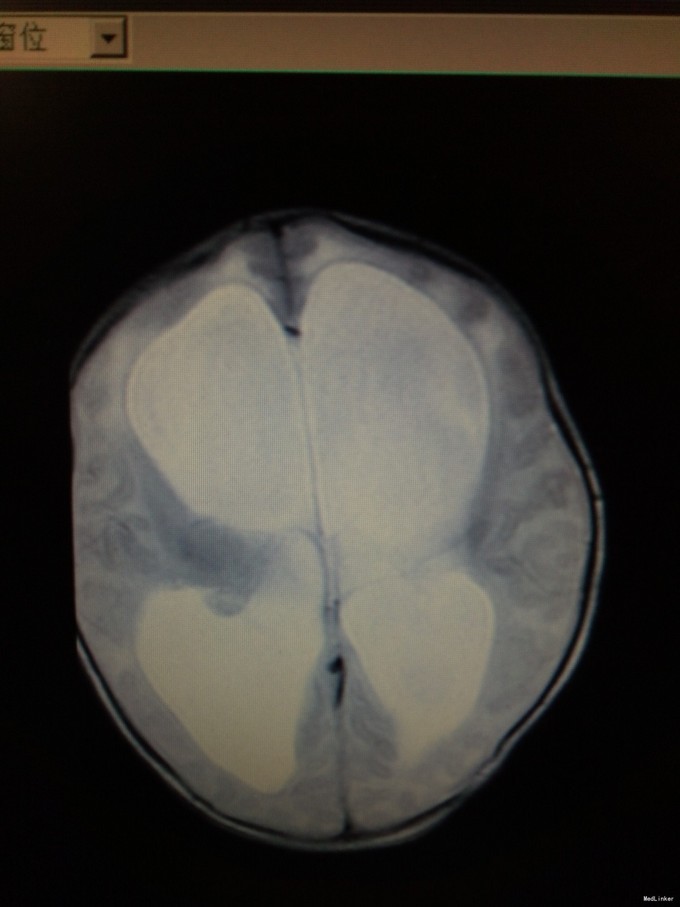

患儿男,29天,因“抽搐1天”入院。患儿足月顺产,出生时无明显异常。其母亲自诉孕期产检无特殊。

查体:发育正常,神清,反应欠佳。前囟3.5*3.5cm,隆起,张力稍高,颅缝分离约0.5cm。双肺呼吸音粗糙,心腹未及明显异常。四肢肌张力稍高,生理反射可引出,病理反射未引出。入院后完善颅脑CT、腰椎穿刺术等,结果如下。

初步诊断为:1.交通性脑积水;2.化脓性脑膜炎。入院后予美罗培南抗感染、营养脑神经、维持内环境平衡等治疗。请神经外科会诊后建议行脑室-腹腔分流术。经近2周治疗后,患儿症状有好转,但病情尚不稳定,家属要求出院,予签字出院。